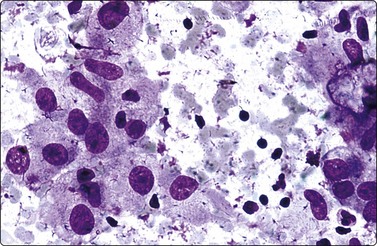

Fluid aspirated from cystic PC is uncharacteristic, brown or resembles altered blood. The diagnosis can easily be missed if well-preserved epithelial cells are scarce (Fig. 6.41).30,31,71 Presence of numerous macrophages, with many in cohesive clusters, should raise a suspicion of PC. Some of these cells are probably degenerating tumor cells exfoliated from the cyst lining (Fig. 6.42). They may represent foam cell metaplasia in tumor cells, and careful scrutiny will usually reveal nuclear features of PC. Large cell size, pseudoinclusions, nuclear grooves, and multiple well-defined vacuoles in atypical histiocytoid cells favor a diagnosis of PC.186

image

Fig. 6.41 Cystic papillary carcinoma

Tumor cells show uniform enlargement with dense cytoplasm and well-defined cell borders. INCIs (Fig. 6.35), characteristic of PC, are seen in up to 90% of cases. They are seen in 5% of the cells (10% if examined under oil immersion under 2–3 planes of focus).164,165 INCIs, however, are not specific to PC as they can be seen in atypical adenomas,166 hyalinizing trabecular tumors,167 MC (see Fig. 6.55),168 AC (see Fig. 6.59) and rarely in FC,90 HT18 and juxta-thyroidal neoplasms (parathyroid adenoma, paraganglioma, etc.).67,90

INCIs have sharp, well-defined, membrane-like margins and are not optically clear but resemble the cytoplasmic color and texture. They probably start as trapped cytoplasm in deep nuclear folds (grooves)169 that eventually invaginate into the nucleus at foci of nuclear membrane weakness. Grooves and inclusions do not usually coexist, possibly due to the pressure of the inclusion unfolding the groove and preventing further groove formation.170 Artifacts such as superimposed air bubbles or fat droplets can mimic INCIs both in PAP- and MGG-stained material.27,171 Optically clear vacuoles and poorly defined central areas of pallor (MGG) should not be accepted as inclusions. The clear or ground-glass (‘Orphan Annie’) nuclei seen in tissue sections are represented in smears by very fine, powdery nuclear chromatin,164 an important diagnostic criterion and a feature best appreciated in ethanol-fixed, PAP-stained smears (Figs 6.35 and 6.36).

Irregular nuclear shapes, convolutions (Fig. 6.35B) and longitudinal nuclear grooves or creases (Fig. 6.36) are visible in cytologic smears (in 85–100% cases) and in sections.165,170 Grooves are obvious in alcohol-fixed material but are difficult to discern in MGG preparations. Strict criteria for recognition have been suggested: continuous grooves or creases, clearly defined and running the length of the nucleus.172 The presence in ≥20% of cells, as counted in selective fields where grooves are frequent, is highly predictive of PC.173 Grooves, however, may be found in small numbers in 70–80% of non-papillary neoplasms, in 50–60% of non-neoplastic thyroid lesions172 and in a variety of extrathyroid tumors; hence, metastatic carcinoma and melanoma are included in differential diagnoses.42

Tumor cells often show delicate soap-bubble like cytoplasmic vacuolation (septate cytoplasmic vacuoles)174or squamoid cytoplasm (metaplastic cells). Dense cytoplasm and well-defined cell margins may simulate Hurthle cells (Fig. 6.37) or squamous cells (Fig. 6.38A). True squamous metaplasia and Hurthle cell change may be present. Cells with abundant vacuolated cytoplasm are seen (Fig. 6.38B) resembling histiocytes (foam cells) but with nuclear features of PC.162 Such ‘foam cell metaplasia’ is seen in about 50% of PCs and is best appreciated at the edges of the smear.42 Foam cell metaplasia may also be seen in cystic NG with papillary hyperplasia42 and in papillary breast lesions. Macrophages and cell debris may be prominent, especially when cystic change is present. Multinucleate giant cells are frequently seen and, if numerous, have been shown to be associated with larger tumor size and greater likelihood of extrathyroidal extension.175 Lymphoid cells are present in 30% of cases.176